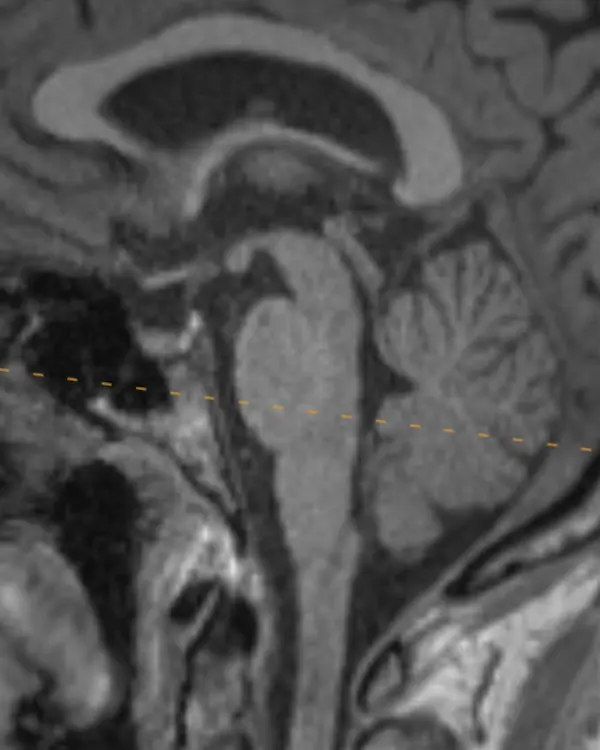

Note that axial planes in brain imaging are not perfectly perpendicular to the brainstem, they are instead created by drawing a line through the anterior commissure (AC) and posterior commissure (PC); the so-called AC-PC line. Keep this in mind when correlating the appearance of structures in the axial plane to sagittal.

The brainstem, outlined in a white dotted line, is divided into the midbrain, pons, and medulla. Each segment has a characteristic appearance that is easiest to recognize in the sagittal plane.

Notice the beak-shaped anterior margin of the midbrain and the cerebrospinal fluid (CSF) space underneath it.

The pons has a bulbous contour anteriorly and a triangular shaped CSF space posterior to it.

The medulla is thin, gradually blends in appearance with the cervical spinal cord, and has a small CSF channel posterior to it.